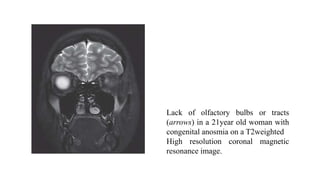

Lack of olfactory bulbs or tracts

(arrows) in a 21year old woman with

congenital anosmia on a T2weighted

High resolution coronal magnetic

resonance image.

• Magnetic resonance imaging (MRI) findings may reveal aplasia or

hypoplasia of the olfactory bulb, or associated encephalocele or

abnormality in the frontal lobe.